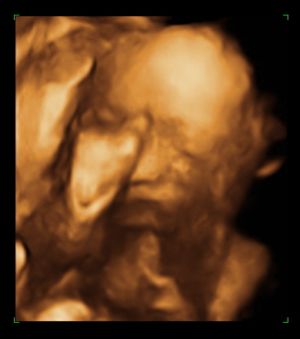

Most én is mutatok képeket, bár korántsem látszik sok minden rajtuk. Sajnos a hátával volt "kifele" így 4D-re sem volt érdemes átkapcsolni. :(

Az arca homloknézetből:

Kép

És a bizonyíték, hoyg kislány (ott bal oldalon fenn látszik a két szeméremajak):